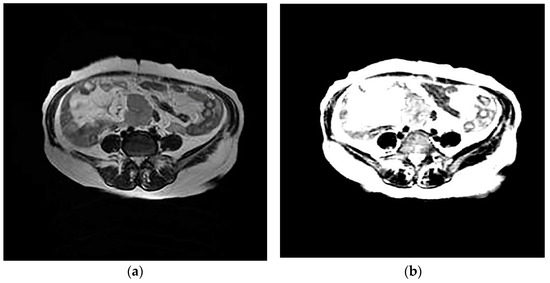

The design of the network can provide the value of image features. The network eliminates redundant information through learners and decoders, and only retains features that can reflect the inherent characteristics of HGSOC, and therefore a small number of features can contain most of the information of tumor images. Therefore, we input T2WI and DWI images from the same patient into the network and reconstructed them into images. It was found that the reconstructed images based on the features were similar to the original images, which proves that the internal features of the images are learned, as shown in Figure 3 and Figure 4.

Figure 3.

Axial T2-weighted image (a); generated image (b).